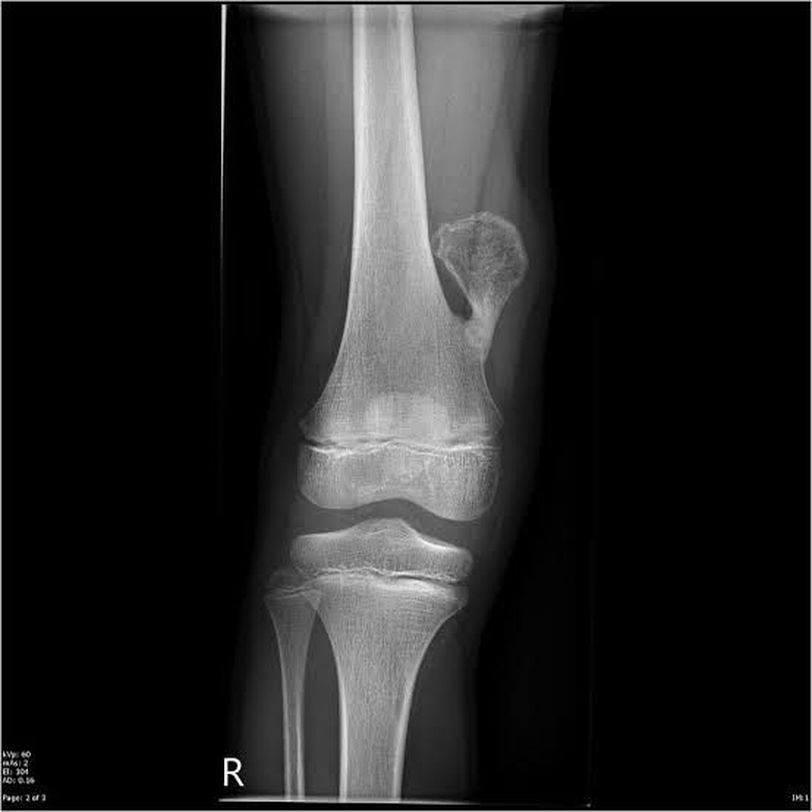

✴️Osteochondroma

🔸Osteochondroma is an overgrowth of bone and cartilage close to the metaphysis of long bone . 🔸 It's the most common benign tumor of bone. 🔸It usually affects people between 10_30 yo. 🔸Affects the two genders at the same rate. . .